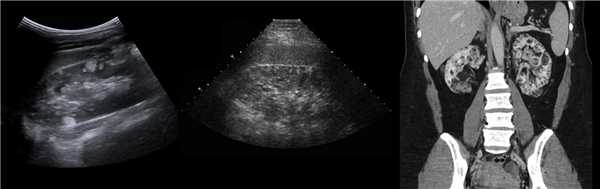

Рисунок. КТ-урография (1) показывает неполное удвоение ЧЛС слева: два мочеточника соединяются на входе в таз и единым мочеточником вступают в мочевой пузырь; внутрипузырная часть мочеточника расширена (красная стрелка) — уретероцеле. Уретероцеле хорошо видно на рентгенограммах (2) при экскреторной урографии: правый мочеточник расширен на всем протяжении, дистальный отдел кистозно расширен — «голова кобры».

Рисунок. Уретероцеле (стрелка) на УЗИ и КТ.

Рисунок. Дистальный отдел мочеточника расширен, в мочевом пузыре анэхогенное образование с тонким и ровным контуром — уретероцеле.